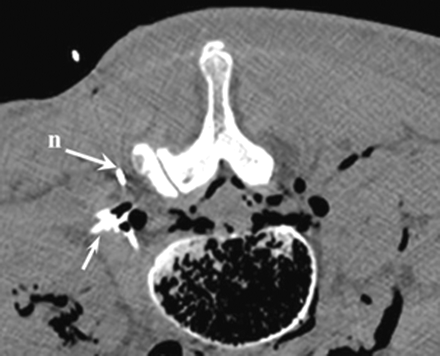

CT confirmed that all 10 needle tips were correctly placed inside the pararadicular compartment, with sufficient contrast accumulation around the respective spinal nerve root (Fig 5). Also in the anatomic dissection and the transverse anatomic cryosections, the needle tips and the blue dye distribution were equally found in the correct pararadicular compartment of each lumbar spinal level. A sufficient pararadicular dye coating of the respective lumbar root was confirmed in all cases without direct needle contact to any nerve root (Figs 6⇓–8).

Corresponding axial CT scan at levels L2-L3, demonstrating the needle and contrast enhancement in the pararadicular area (arrow).